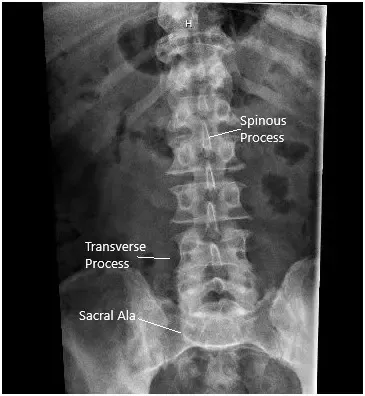

La radiografía en vistas AP y laterales mostró el estrechamiento del disco L5-S1